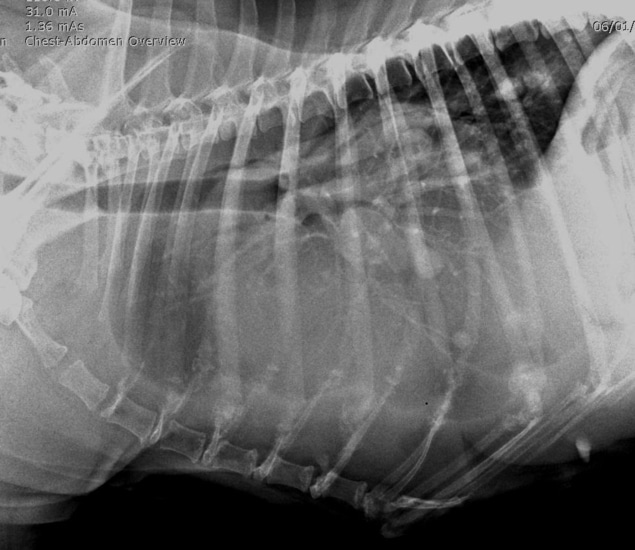

Un examen radiographique est réalisé sur animal vigile. Le coude gauche présente une dégradation arthrosique déjà avancée que l’on retrouve également sur le coude droit. Une déformation des tissus mous est visible en regard de la portion caudale de la scapula. L’articulation scapulo-humérale ne présente pas d’anomalie, seule la scapula présente des modifications de son architecture sur sa face interne avec une corticale effacée, une association d’ostéolyse et d’ostéoproduction (fig. 2 et 3).